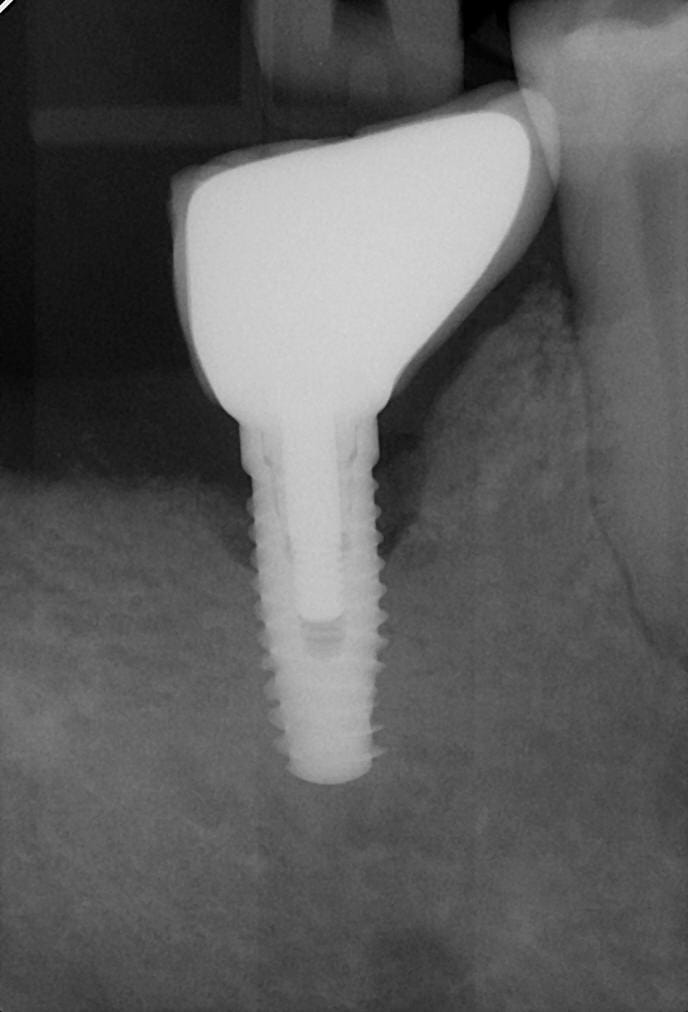

CT

06/08/2019 à 11h36

Bonjour,

également besoin de votre aide, je penche pour des biomet 3i certain, mais pas sûr.

Sc1 s637nu - Eugenol

Sc2 gnqvve - Eugenol

Oui c’est bien cela 100% sûr

Au passage vous pouvez admirer la perte d’os qui est souvent présente sur ces implants « grandes marques » qui coûtent la peau du cul , avec notamment ce type d’anatomie avec un col large qui n’est pas dans le prolongement du corps de l’implant. Je n’en dirais pas plus c’est du sérieux puisque c’est Une grande marque ....... :) pour peu qu’i y ait un problème de pose, et un garde manger entre l’implant et la dent , et là on est encore plus certain de perdre de l’os

Effectivement il s'agit bien d'un 3i. Selon la couleur, bleu 4mm ou jaune 5mm.